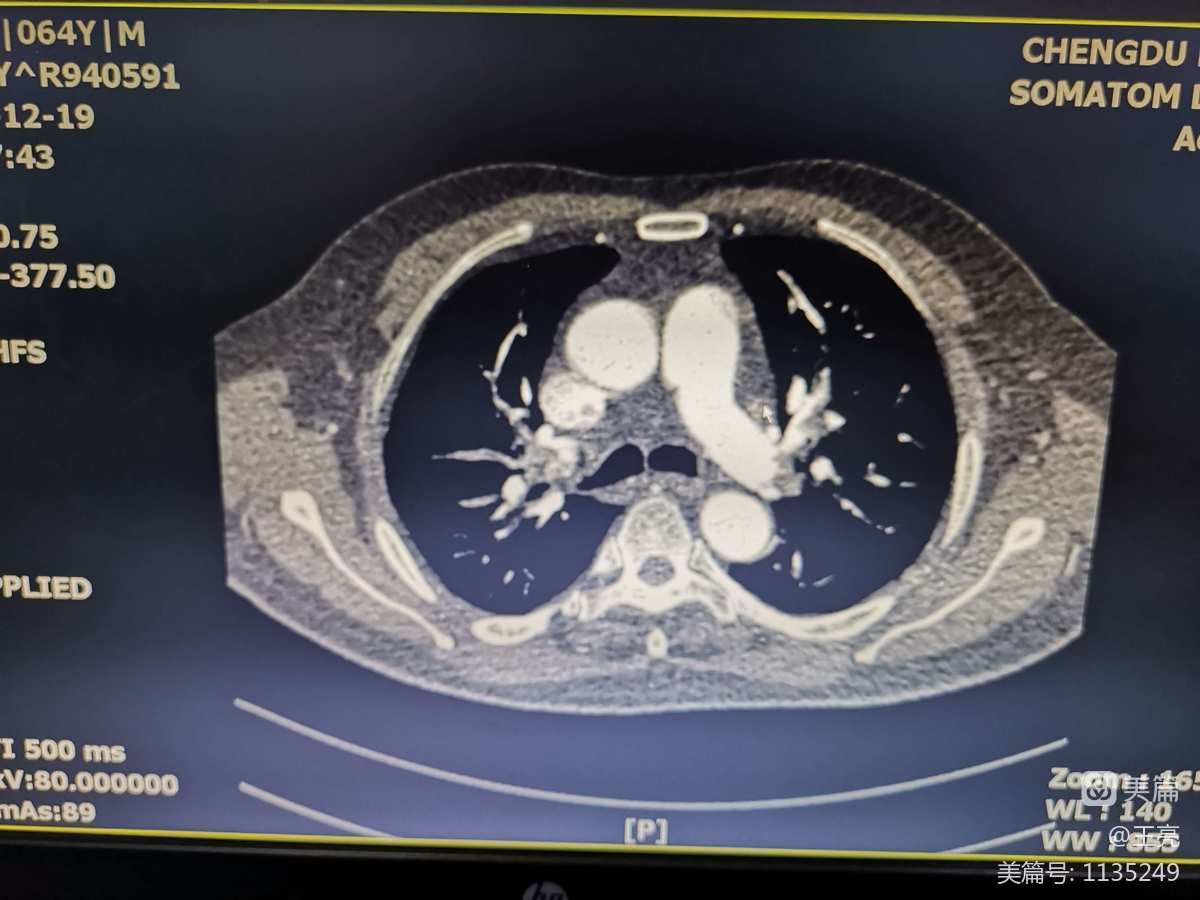

胸片中有主肺动脉扩张,右心室增大,肺野透亮和胸腔渗出。血气的特点是动脉低氧血症和过度通气。心脏超声和右心导管显示慢性肺动脉高压。

在这种患者内科治疗的效果是不理想的。因此,对于怀疑慢性肺栓塞引起肺动脉高压的患者应行肺动脉造影,肺扫描的灌注异常提供诊断的根据,解剖部位,肺动脉压力,选择适当的患者行血栓内膜切除术,能取得很好的结果。